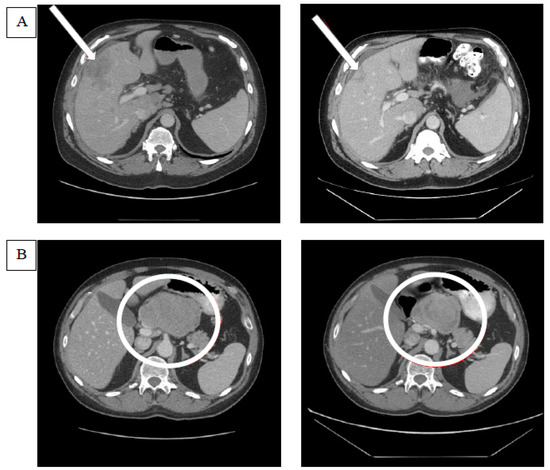

Figure 2.

Examples of tumor responses after glembatumumab vedotin treatment. (A) The computerized tomography (CT) scan on the left indicates the baseline target lesion in the liver parenchyma that is pointed at by an arrow. The CT scan image on the right demonstrates the shrinkage in the target lesion after glembatumumab vedotin (GV). (B) The CT scan on the left demonstrates the target lesion in the porta hepatis lymph node, and the one on the right shows the changes in the lesion after GV. Though the lesion appears to have shrunk in size, the decrease in the lesion’s short axis was not sufficient to meet the response criteria of RECIST 1.1. The target lesion response in the right panel was classified as a stable disease.